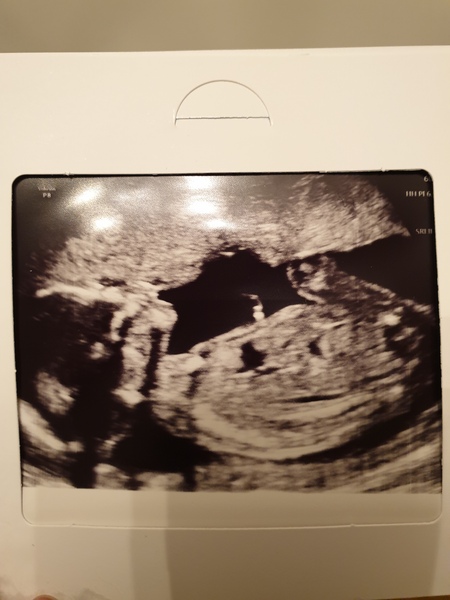

lc86 · 15/07/2020 22:23

Haven't been on here for a few days as lots going on! However finally had our anomaly scan today ☺️ sadly dh couldn't come in but was still amazing to know everything is as it should be and baby is growing nicely 💙 hoping to book a 4d one in a few weeks if it's allowed

👣 Due Nov/Dec 👣 it's the 20 week scans! 👣

Also found out the placenta is anterior and that's why I haven't felt much movement.. baby has legs crossed on the scan, wouldn't keep still for his selfie lol xx

@lc86 that's such a beautiful and clear scan photo, so sorry your partner wasn't allowed in with you but it's such a relief afterwards, and that's a really lovely photo 🥰